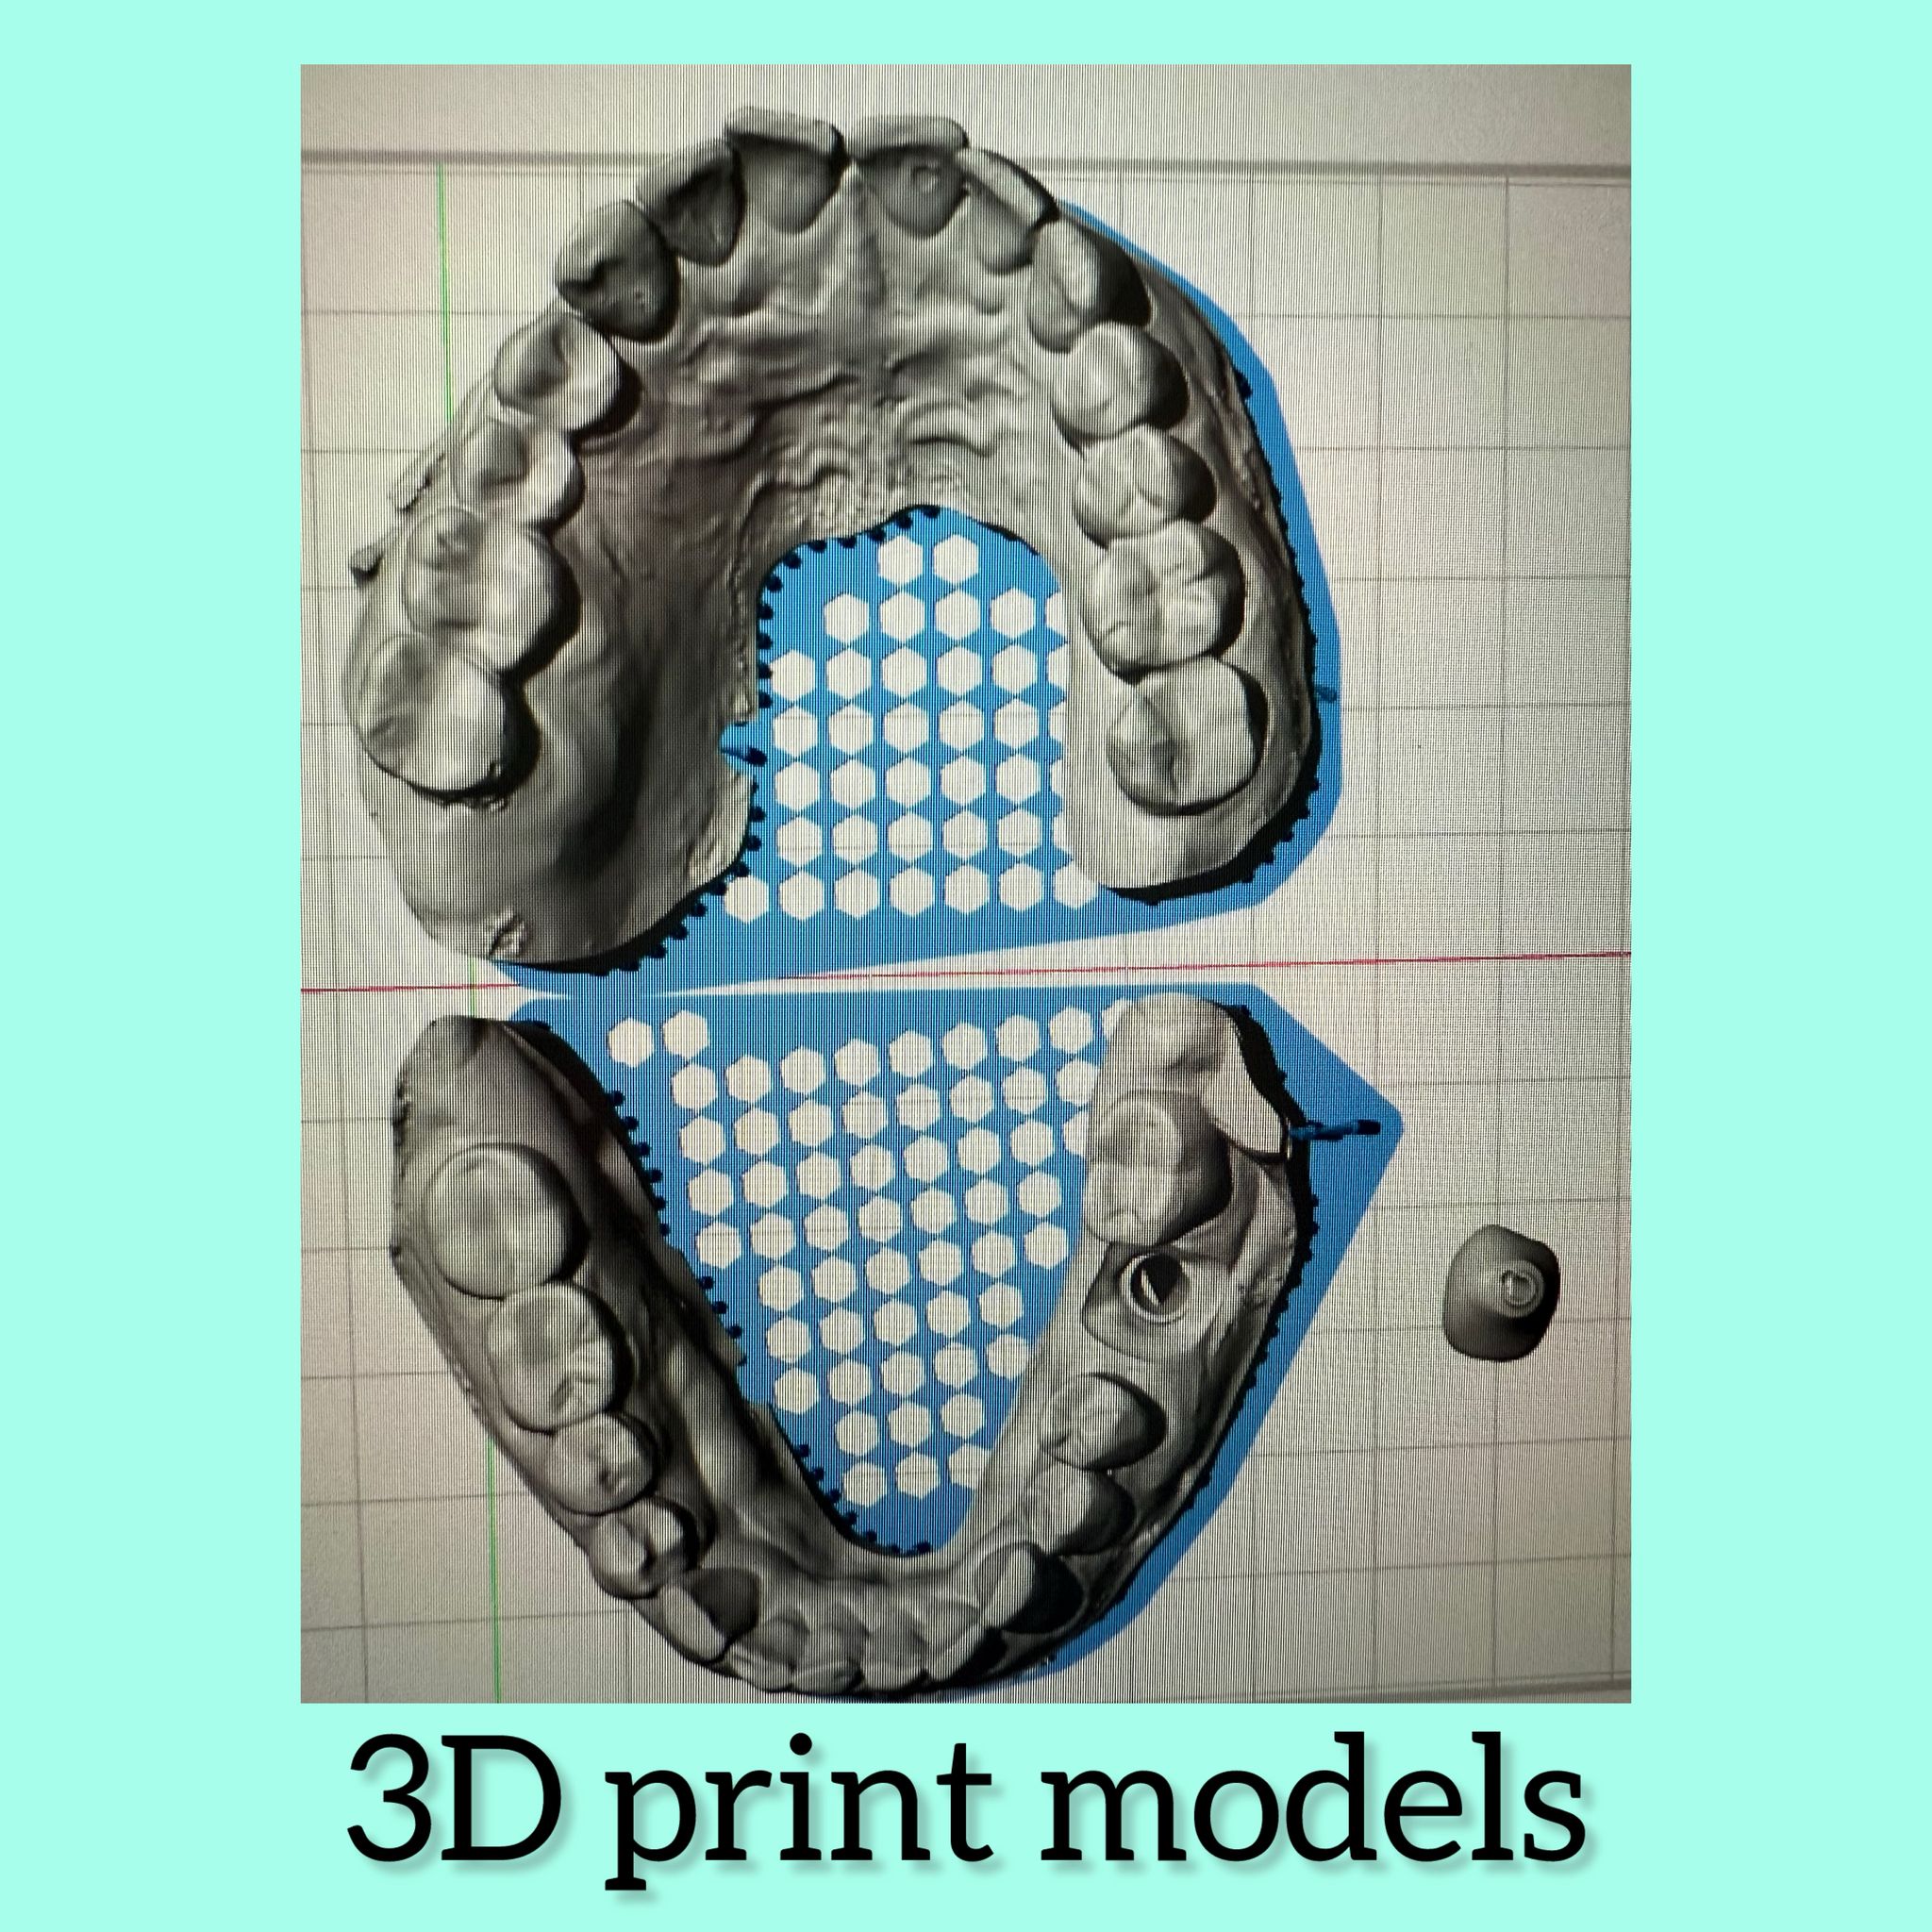

Dental Laboratorium in Amsterdam

Dental Laboratorium in Amsterdam